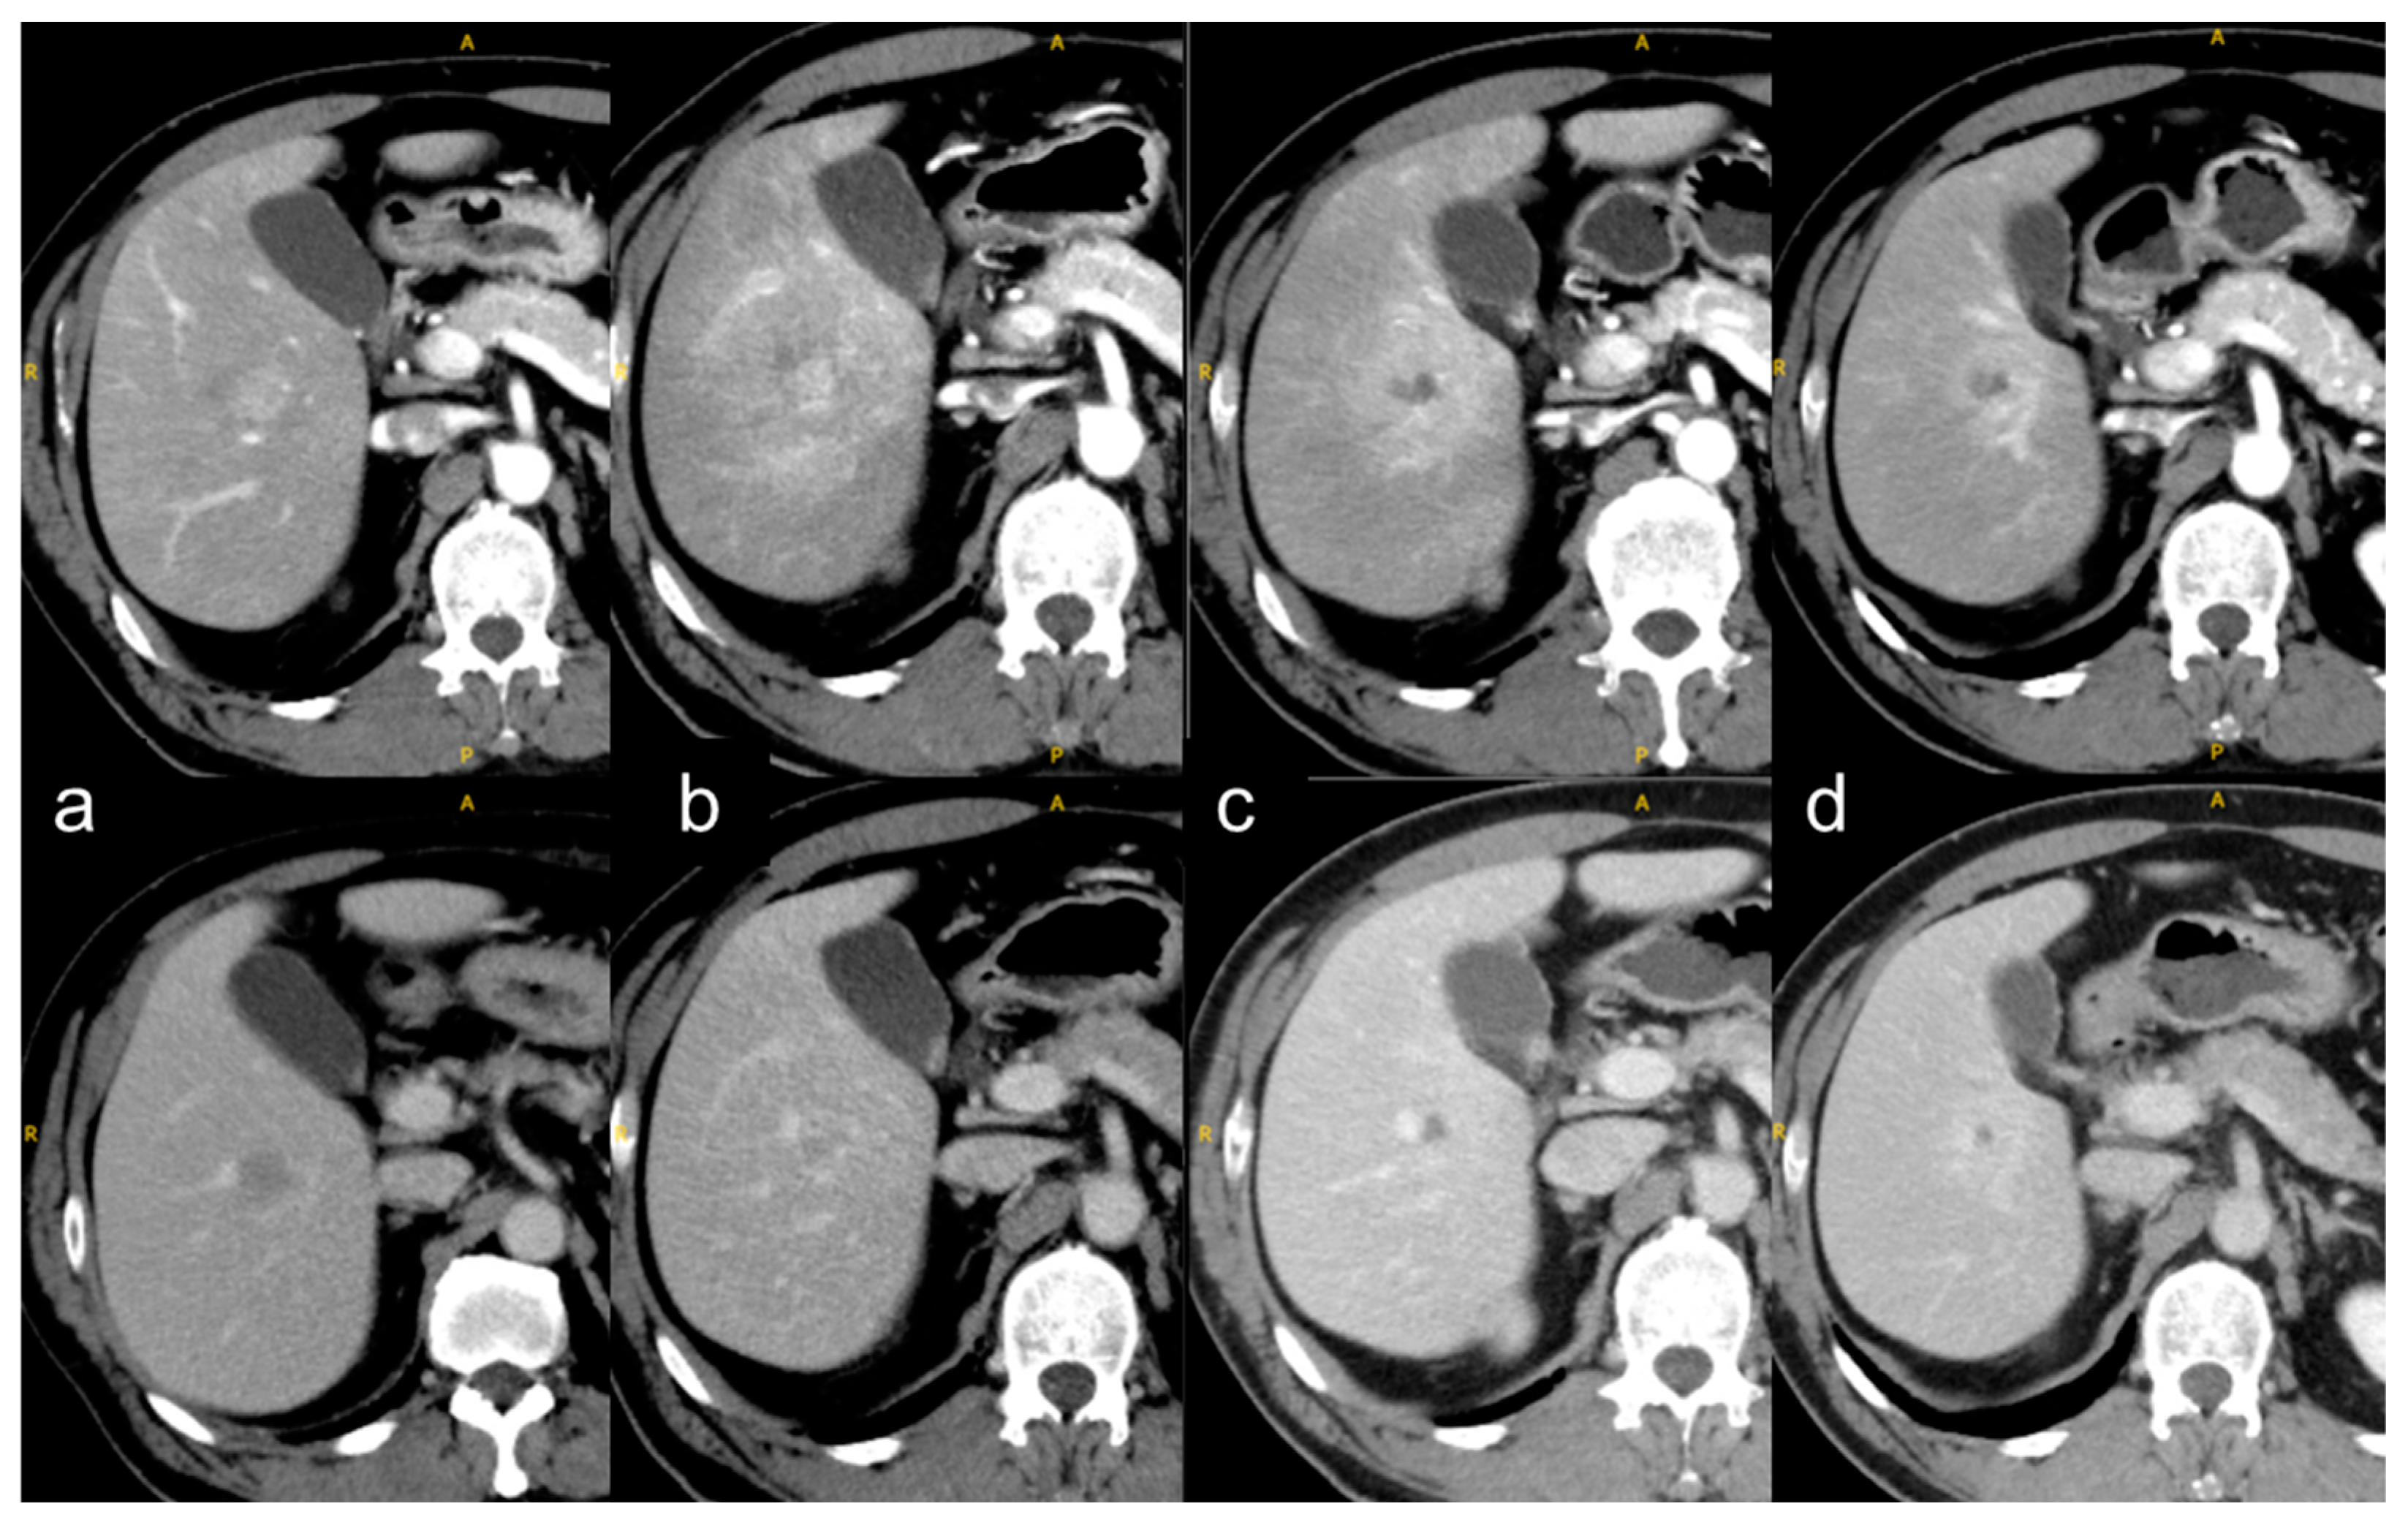

- Kimura, T.; Takahashi, S.; Kenjo, M.; Nishibuchi, I.; Takahashi, I.; Takeuchi, Y.; Doi, Y.; Kaneyasu, Y.; Murakami, Y.; Honda, Y.; et al. Dynamic computed tomography appearance of tumor response after stereotactic body radiation therapy for hepatocellular carcinoma: How should we evaluate treatment effects? Hepatol. Res. 2013, 43, 717–727. [Google Scholar] [CrossRef] [PubMed]

- Sanuki, N.; Takeda, A.; Mizuno, T.; Oku, Y.; Eriguchi, T.; Iwabuchi, S.; Kunieda, E. Tumor response on CT following hypofractionated stereotactic ablative body radiotherapy for small hypervascular hepatocellular carcinoma with cirrhosis. AJR Am. J. Roentgenol. 2013, 201, W812–W820. [Google Scholar] [CrossRef] [PubMed]

- Takeda, A.; Oku, Y.; Sanuki, N.; Kunieda, E.; Koike, N.; Aoki, Y.; Ohashi, T.; Iwabuchi, S.; Takatsuka, K.; Takeda, T.; et al. Dose volume histogram analysis of focal liver reaction in follow-up multiphasic CT following stereotactic body radiotherapy for small hepatocellular carcinoma. Radiother. Oncol. 2012, 104, 374–378. [Google Scholar] [CrossRef]

- Sanuki-Fujimoto, N.; Takeda, A.; Ohashi, T.; Kunieda, E.; Iwabuchi, S.; Takatsuka, K.; Koike, N.; Shigematsu, N. CT evaluations of focal liver reactions following stereotactic body radiotherapy for small hepatocellular carcinoma with cirrhosis: Relationship between imaging appearance and baseline liver function. Br. J. Radiol. 2010, 83, 1063–1071. [Google Scholar] [CrossRef]

- Herfarth, K.K.; Hof, H.; Bahner, M.L.; Lohr, F.; Höss, A.; van Kaick, G.; Wannenmacher, M.; Debus, J. Assessment of focal liver reaction by multiphasic CT after stereotactic single-dose radiotherapy of liver tumors. Int. J. Radiat. Oncol. Biol. Phys. 2003, 57, 444–451. [Google Scholar] [CrossRef]

- Kimura, T.; Takahashi, S.; Takahashi, I.; Nishibuchi, I.; Doi, Y.; Kenjo, M.; Murakami, Y.; Honda, Y.; Aikata, H.; Chayama, K.; et al. The time course of dynamic computed tomographic appearance of radiation injury to the cirrhotic liver following stereotactic body radiation therapy for hepatocellular carcinoma. PLoS One 2015, 10, e0125231. [Google Scholar] [CrossRef]